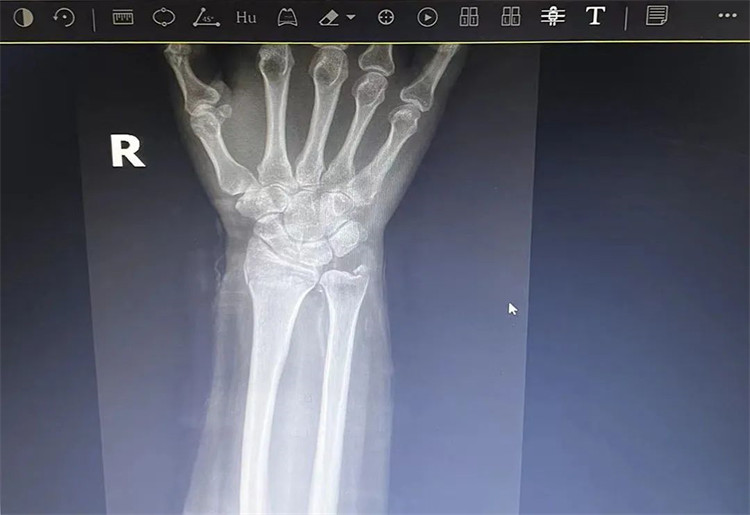

患者老年女性,50多歲,在騎電動(dòng)車停下時(shí)因電動(dòng)車倒下,右手著地,當(dāng)即感覺,右腕及骶尾部腫痛伴右關(guān)節(jié)畸形、活動(dòng)受限,急來我院就診。門診醫(yī)師結(jié)合病史、查體及輔助檢查后,診斷為:右橈尺骨遠(yuǎn)端骨折、骶尾部挫傷并收入住院部。

患者入院后,中醫(yī)正骨科副主任鄭斌斌,認(rèn)真查體及分析檢查結(jié)果后,考慮患者老年女性,建議患者采用拔伸牽引、端提、捺正等閉合手法復(fù)位后,行夾板固定,多能獲得較好療效?;颊邚?fù)位固定后,疼痛明顯減輕。避免了手術(shù)帶來的痛苦及手術(shù)開刀所需費(fèi)用。